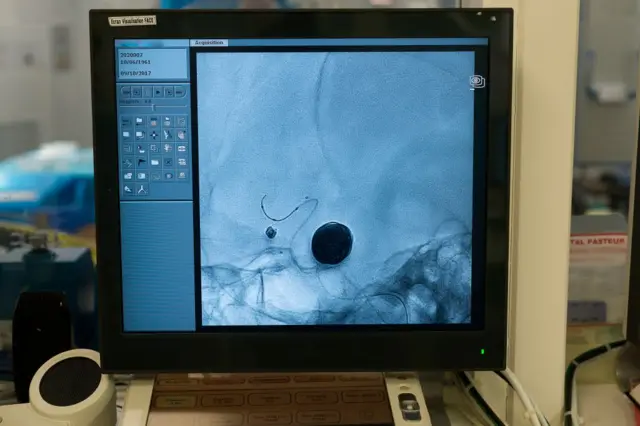

பட மூலாதாரம், Dr Ianjcheralathan

மருத்துவம் மிகவும் நவீனமாகிவிட்ட காலத்தில் நாம் இருக்கிறோம். அன்யூரிச இரத்த நாள வீக்கங்களுக்கான , நுண்துளை (Endovascular)ரத்த நாள சிகிச்சைகளும் உள்ளன. அதனால் தீவிர நிலையில் சிகிச்சைக்கு செல்வதற்கு பதிலாக, ஆரம்பக்கட்டத்தில் கண்டறிவது சிறந்தது,''என்றும் அவர் தெரிவித்தார்.